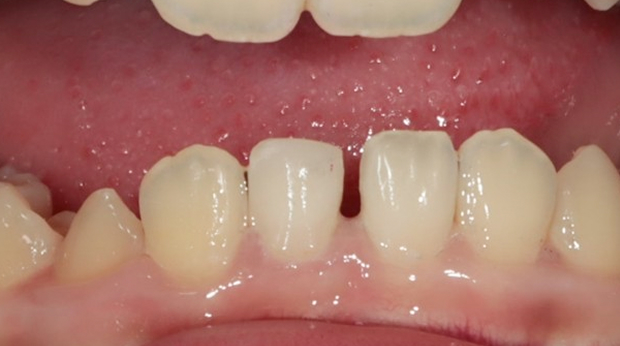

라미네이트